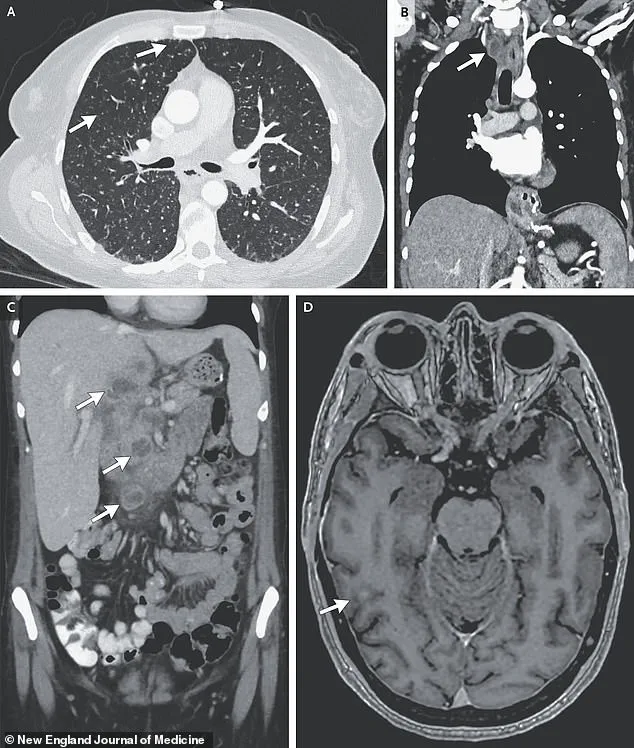

Doctors observed worsening oxygen levels and labored breathing, prompting a series of scans.

X-rays revealed small nodules in her lungs, a telltale sign of bacterial infection.

Further imaging uncovered lesions in her liver, lymph nodes, pancreas, and brain—indications that the infection had spread far beyond her respiratory system.

Consider the case of a woman whose medical scans revealed nodules in multiple organs, including her lungs, liver, pancreas, and brain.

These images, captured through advanced imaging techniques, illustrated the insidious nature of the disease.

TB in the brain can lead to catastrophic outcomes, damaging vital tissues and increasing pressure within the skull.

This pressure can cause nerve cells to die, resulting in paralysis, strokes, or even death.

Such cases highlight the importance of early detection and treatment, as the disease’s ability to infiltrate and damage organs beyond the lungs makes it particularly dangerous if left unchecked.